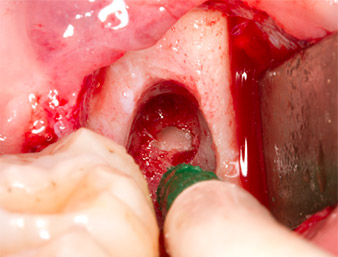

Das Gewebe über dem Wurzelrest war nicht vollständig verknöchert und bestand zu einem großen Teil aus entzündlich verändertem Granulationsgewebe (Abb. 4).